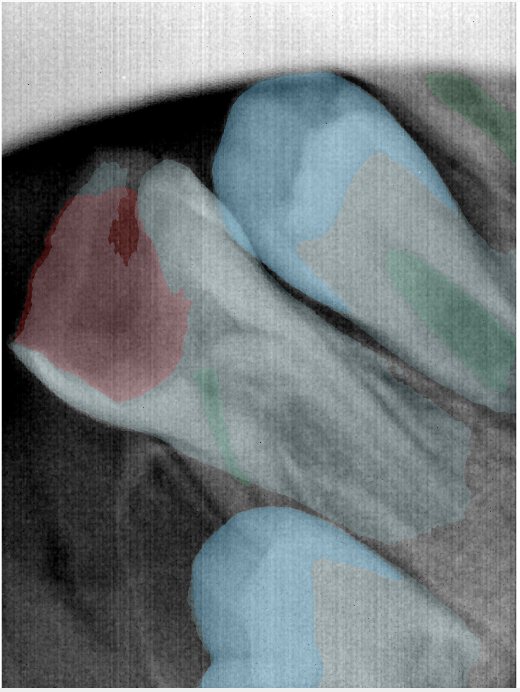

CR/DR 牙齿分割阶段记录

当前进展

- 完成了 CR/DR 牙齿相关分割训练

- 当前结果已经达到阶段预期,但仍有细节问题需要继续处理

相关测试

遇到的问题

- 训练过程中出现过 mask 下移问题

- 部分结果会出现 box 填充异常

- mask 边缘仍然有比较明显的锯齿感

参考

第二版算法问题测试